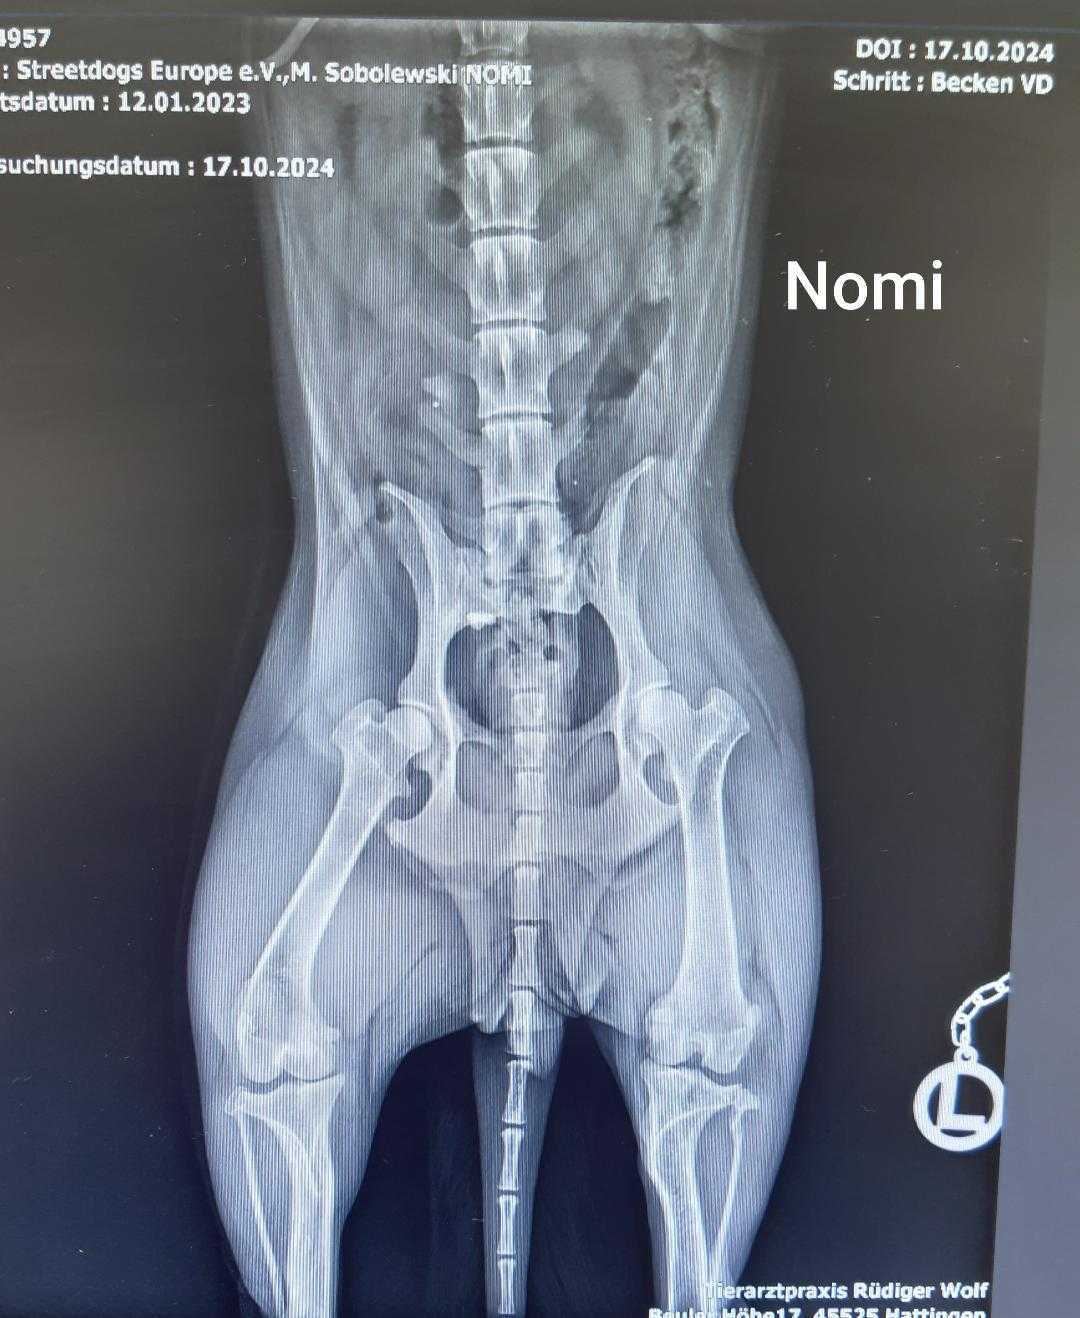

Hier seht ihr jetzt auch meine Innenfotos - da erkenne ich mich überhaupt nicht. Ich verstehe auch nicht, warum es so interessant ist, sich meine Knochen anzugucken. Aber für euch Menschen scheinen die sehr interessant zu sein.

Vorhin hat mein Pflegefrauchen mit meiner neuen Besitzerin, Annette, telefoniert. Da hab ich mitbekommen, dass mein Knie operiert wurde. Da hat der Doc irgendwas passend gefräst, einen Knochen gekürzt und die Kniescheibe in der richtigen Position befestigt. Morgen ist Kontrolle und da gibt es dann auch die Röntgenbilder.

Ich muss mich wirklich noch ein paar Tage erholen und werde euch daher am Montag berichten wie es mir geht und dann seht ihr auch die Röntgenbilder.